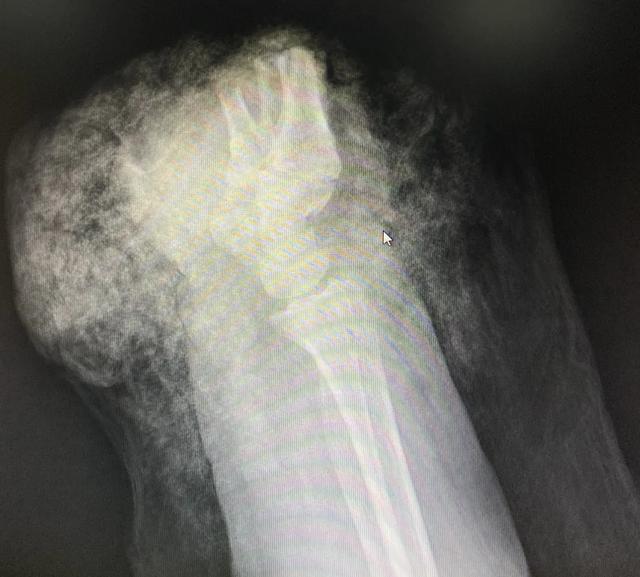

断掌正面CT图

树兰杭州医院医生奋战 5 小时,断掌残垣成功再植

断掌侧面CT图

“因牵牛而导致断手的病例还是头一次看到。”树兰(杭州)医院手足显微外科黎斌副主任医师接诊后表示:“伤者由于手掌被麻绳勒紧,受到前后牵拉力同时作用而造成手掌骨头、肌腱及神经组织断裂,属于非常严重的旋转撕脱离断伤。”

黎斌副主任介绍介绍,手足显微外科经常会接诊被机器或者刀具砍伤的手部受损,断面比较整齐,但张奶奶这种撕扯伤有很多缺损组织,因拉扯被抽出的肌腱长度达20多厘米,比砍断更严重,大大增加了再植手术的难度,因此当时伤者送到医院时已经面临截肢的危险。